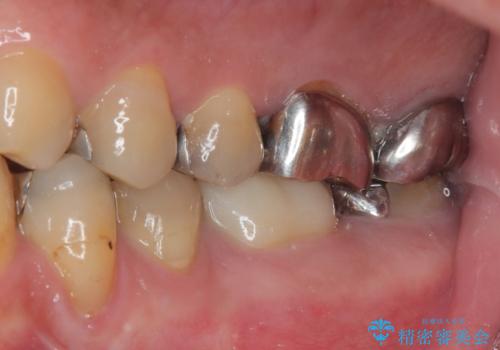

- 近医にてむし歯治療として根管治療を受けるも、痛みが全く改善しないとのことで来院された患者様です。

痛みが継続するため、「根管治療」と検索したところ、「ラバーダム」の重要性を知るところとなったようです。

根管治療を実施した後に、フルジルコニアクラウンにて補綴することとしました。

大臼歯の治療後に海外赴任され、数年ぶりに帰国されました。

奥歯に痛みがあるとのことで診察を行ったところ、海外(アメリカ)にて処置をした手前の歯が既に失活していることが分かりました。なお、治療を行った大臼歯はレントゲン写真上の治癒が認められました。

症状のあった歯に対しても根管治療を行い、同様に補綴治療を行いました。